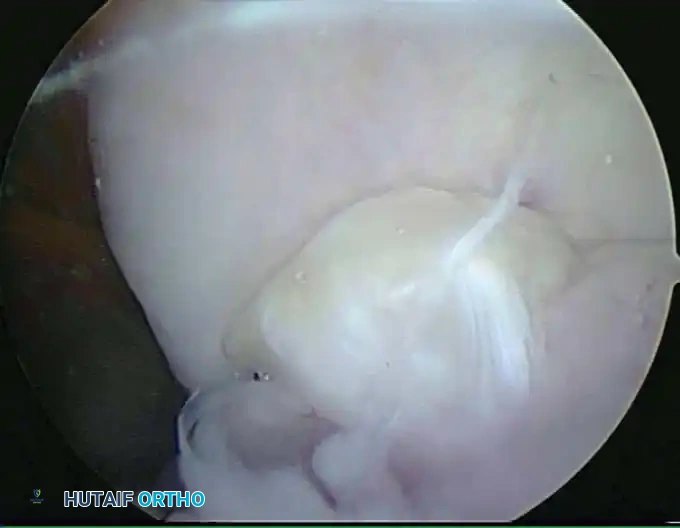

Anterior Portals

The Anterolateral Portals:

Traditionally the standard diagnostic portal, the anterolateral portal is established after joint distention. There are three variations:

1. Distal Anterolateral: 2 to 3 cm distal and 1 cm anterior to the lateral epicondyle.

2. Midanterolateral: Just proximal and 1 cm anterior to the palpable radiocapitellar joint.

3. Proximal Anterolateral: 2 cm proximal and 1 cm anterior to the lateral epicondyle (described by Field et al.).

The anterolateral portal traverses the extensor carpi radialis brevis (ECRB) muscle and passes beneath the radial nerve.

Surgical Pitfall: The radial nerve is at extreme risk during anterolateral portal placement. Lynch et al. demonstrated that instruments may pass within 4 mm of the radial nerve in an undistended elbow. However, with 90 degrees of flexion and maximal joint distention, the distance increases to an average of 11 mm.

Field et al. found the safety margin is greatest with the proximal anterolateral portal (13.7 mm), followed by the midanterolateral (10.9 mm), and least with the distal anterolateral portal (7.2 mm).

Surgical Technique for Portal Entry:

Skin incisions must be made superficially with a No. 11 blade to protect the lateral and posterior antebrachial cutaneous nerves. A small hemostat is used to bluntly spread the soft tissues down to the capsule before a blunt trocar is introduced into the joint.